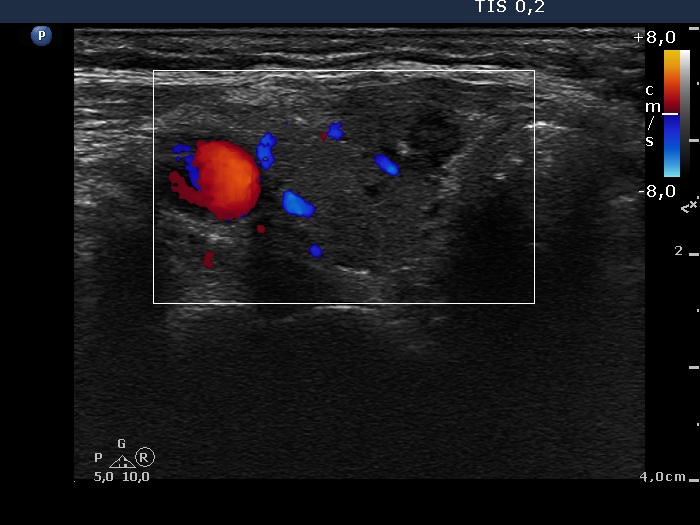

Ultrasonography. There was a hypoechogenic nodule presenting microcalcification in the ventromedial part of the right thyroid. According to the palpable mass in the right submandibular area a lymph node was found. The node did not presented hilum.